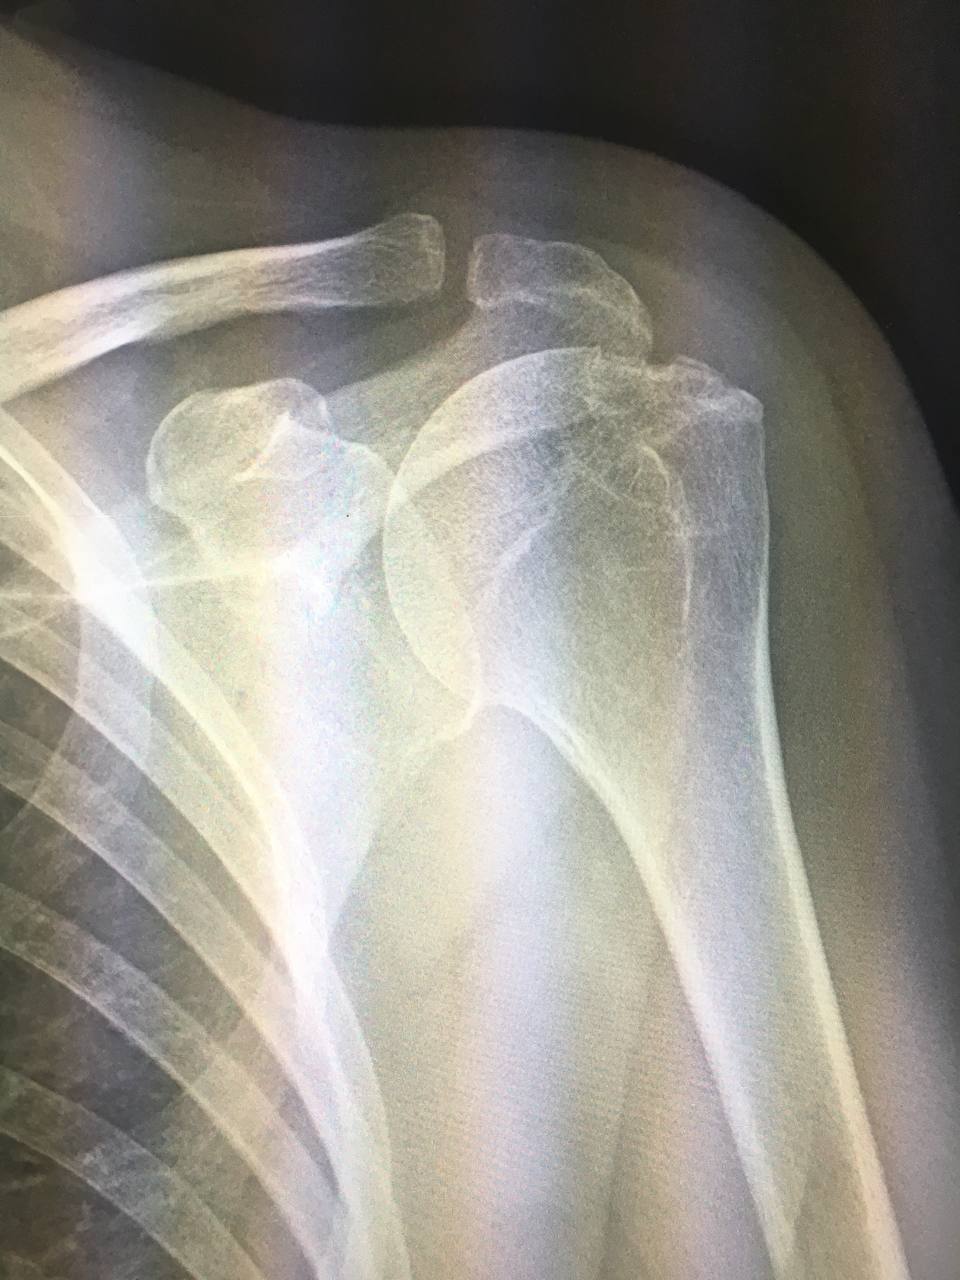

Ж, 60 л, боль в суставе. Хилл-сакс? Смущает участок над большим бугорком

Да, он самый ,скорее всего не свежий